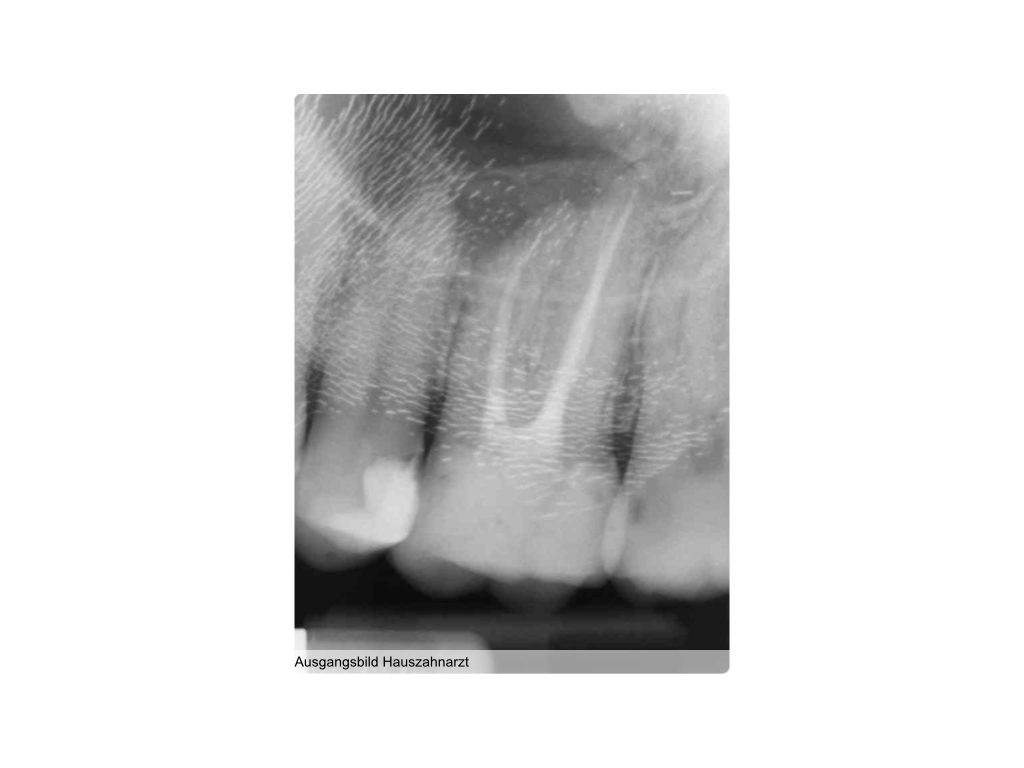

WS8.001

1024 × 768

Instrumentenfraktur (3a)